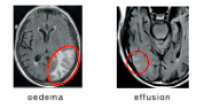

ARIA-E (vasogent ödem och effusion)

Plasmaläckage syns på FLAIR-sekvenser (Fluid-Attenuated Inversion Recovery) vid MR medan mikroblödningar och sideros detekteras på T2*-viktad MR, se tabell nedan för en diagnostisk jämförelse mellan ARIA-E och ARIA-H.1,2,4

| Primär diagnostisk bildsekvens | T2-FLAIR>![]() |

| Diagnostiska fynd | Förhöjd signalintensitet på FLAIR-bilder, ingen diffusionbegränsning2 | Väldigt låg signalintensitet på T2*GRE-bilder1,4 |

| Karaktär på läckageprodukter | Proteinrika vätskor4 | Nedbrytningsprodukter av blod4 |

| Lokalisering av ökad vaskulär permeabilitet | Parenkym: vasogent ödem Leptomeninger: sulkala effusioner4 |